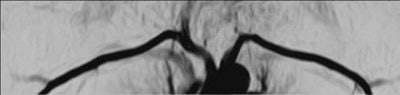

![]() |

| Noncontrast-enhanced vascular imaging on a 1.5-tesla scanner (Achieva). Left, gated subtraction MRA. Top right, digital subtraction angiography. Bottom right, CT angiography. Images courtesy of Philips Medical Systems North America and Hyogo Brain and Heart Center, Hygogo, Japan. |